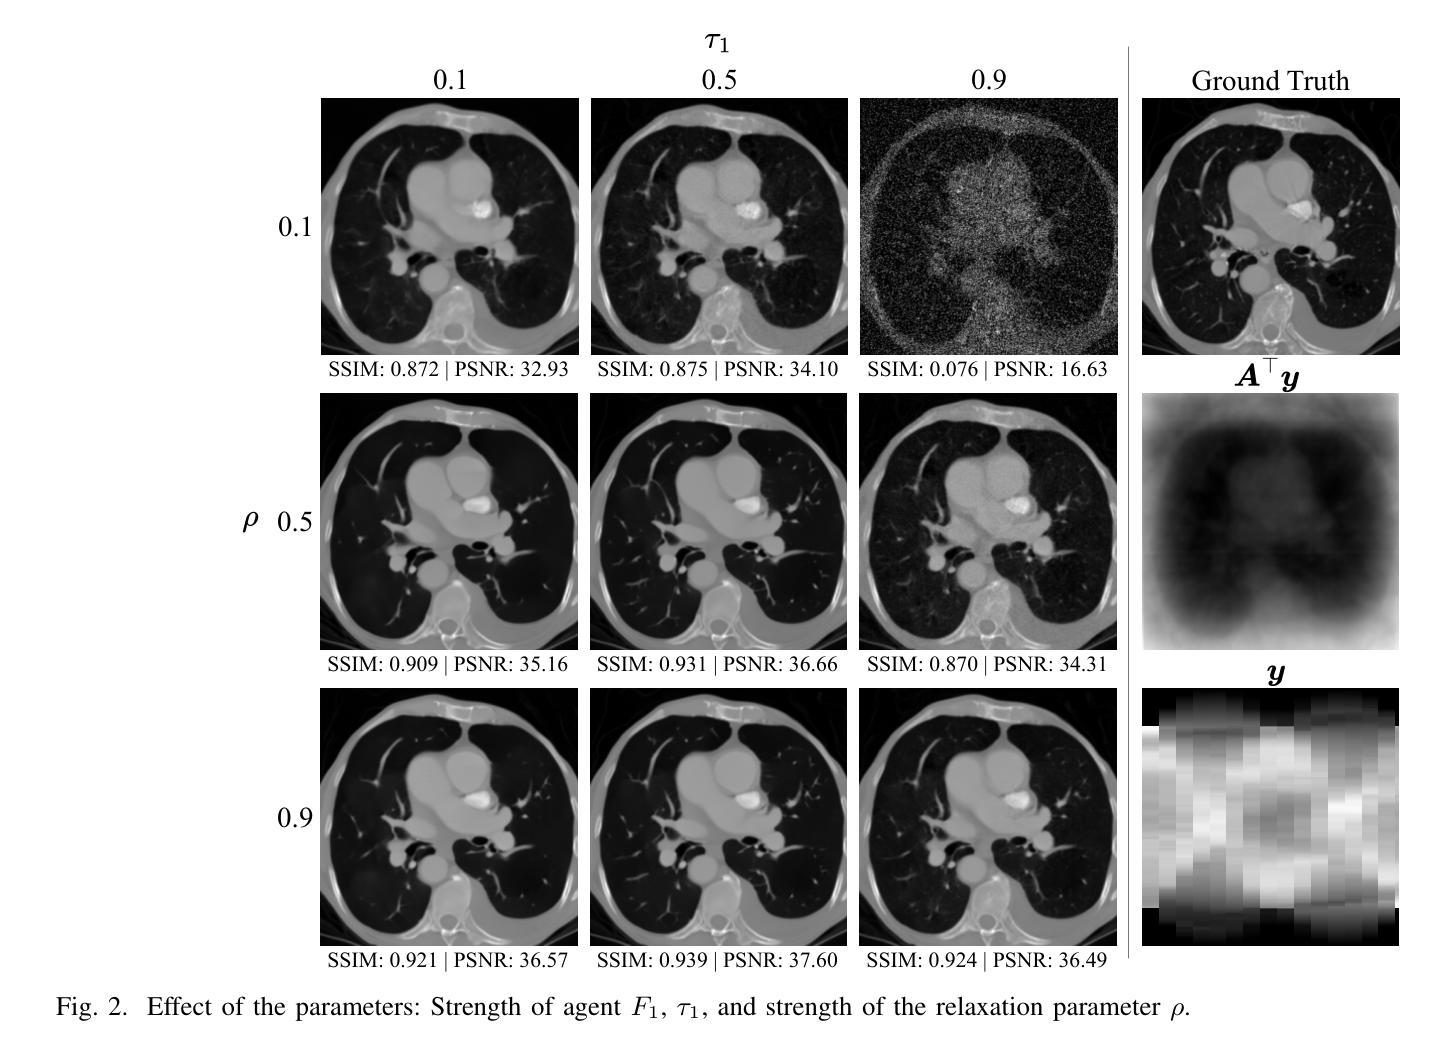

DICE: Diffusion Consensus Equilibrium for Sparse-view CT Reconstruction

Sparse-view computed tomography (CT) reconstruction is fundamentally challenging due to undersampling, leading to an ill-posed inverse problem. Traditional iterative methods incorporate handcrafted or learned priors to regularize the solution but struggle to capture the complex structures present in medical images. In contrast, diffusion models (DMs) have recently emerged as powerful generative priors that can accurately model complex image distributions. In this work, we introduce Diffusion Consensus Equilibrium (DICE), a framework that integrates a two-agent consensus equilibrium into the sampling process of a DM. DICE alternates between: (i) a data-consistency agent, implemented through a proximal operator enforcing measurement consistency, and (ii) a prior agent, realized by a DM performing a clean image estimation at each sampling step. By balancing these two complementary agents iteratively, DICE effectively combines strong generative prior capabilities with measurement consistency. Experimental results show that DICE significantly outperforms state-of-the-art baselines in reconstructing high-quality CT images under uniform and non-uniform sparse-view settings of 15, 30, and 60 views (out of a total of 180), demonstrating both its effectiveness and robustness.

稀疏视图计算机断层扫描(CT)重建面临根本挑战,因为欠采样导致反问题不适定。传统迭代方法结合手工或学习先验来正则化解决方案,但难以捕捉医疗图像中存在的复杂结构。相比之下,扩散模型(DMs)最近作为强大的生成先验出现,可以准确地模拟复杂的图像分布。在这项工作中,我们引入了扩散共识平衡(DICE),这是一个将两智能体共识平衡集成到扩散模型的采样过程中的框架。DICE在以下两个智能体之间交替进行:(i)数据一致性智能体,通过近端算子强制实施测量一致性来实现;(ii)先验智能体,通过每个采样步骤中执行清洁图像估计的扩散模型实现。通过迭代平衡这两个互补的智能体,DICE有效地结合了强大的生成先验能力和测量一致性。实验结果表明,无论是在统一和非统一的稀疏视图设置下,DICE在重建高质量CT图像方面都显著优于最新基线,即在总共180个视图中仅使用15、30和60个视图,证明了其有效性和稳健性。

Summary

本文介绍了一种名为Diffusion Consensus Equilibrium(DICE)的框架,该框架结合了扩散模型(DMs)的强大生成先验和测量一致性。DICE通过在采样过程中采用双智能体共识均衡机制,实现了数据一致性智能体和先验智能体的交替作用。这种方法在稀疏视图计算机断层扫描(CT)重建中表现优异,显著优于现有基线,能够在均匀和非均匀稀疏视图设置下重建高质量CT图像。

Key Takeaways

- 扩散模型(DMs)作为强大的生成先验,能够准确地模拟复杂的图像分布。

- DICE框架结合了数据一致性智能体和先验智能体,通过迭代平衡两者来实现高效的CT图像重建。

- DICE框架通过采用双智能体共识均衡机制,在采样过程中实现了强大的生成先验与测量一致性结合。

- DICE在稀疏视图CT重建中表现出显著优势,能够在不同视图设置下重建高质量图像。

- DICE框架在均匀和非均匀稀疏视图设置下均表现出有效性和稳健性。

- 传统迭代方法在手工艺或学习先验方面存在挑战,无法完全捕捉医疗图像的复杂结构,而DICE框架能够克服这些挑战。